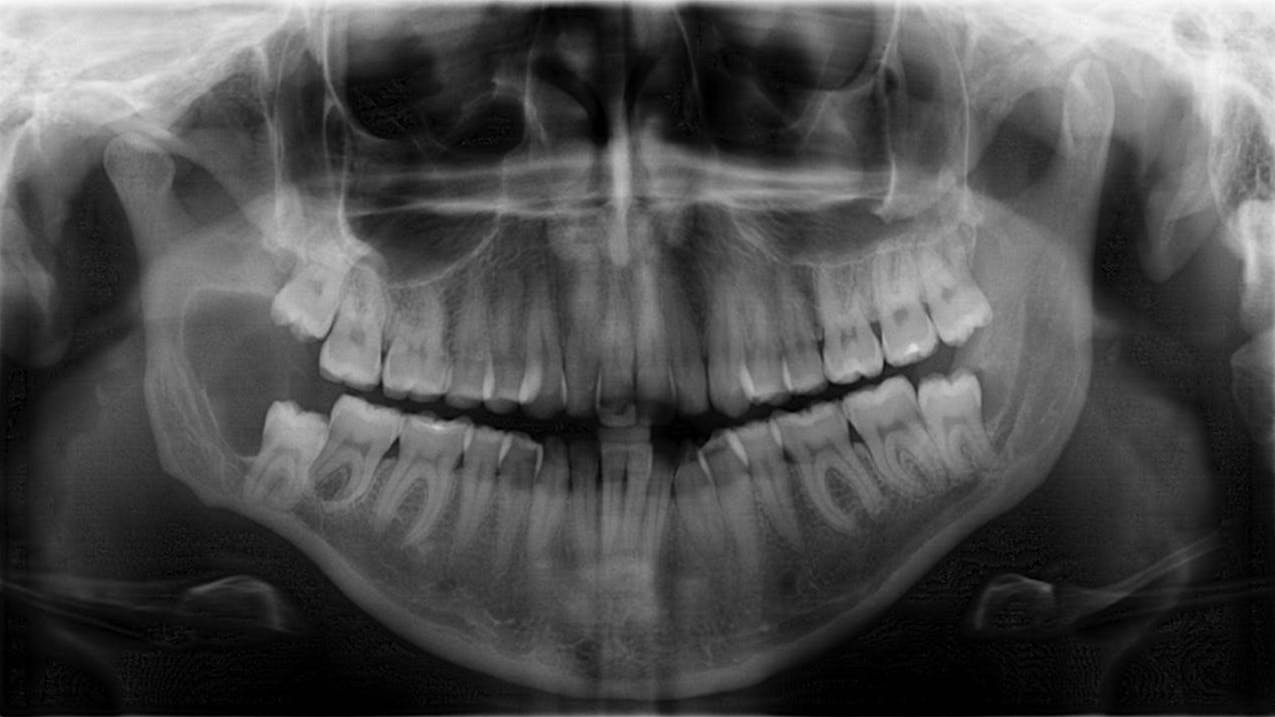

The patient is referred to the oral surgeon for immediate surgery with enucleation. A specimen is sent to the lab for pathology, and a liquid diet is recommended for six to eight weeks (figure 3).

Bone has filled in, no paresthesia is present, and there are no recurrent lesions or abnormal cell formation. No. 17 will be monitored closely with plans for removal when the bone on the right side has healed sufficiently. Three-month (figure 4) and six-month (figure 5) radiographs are shown below.